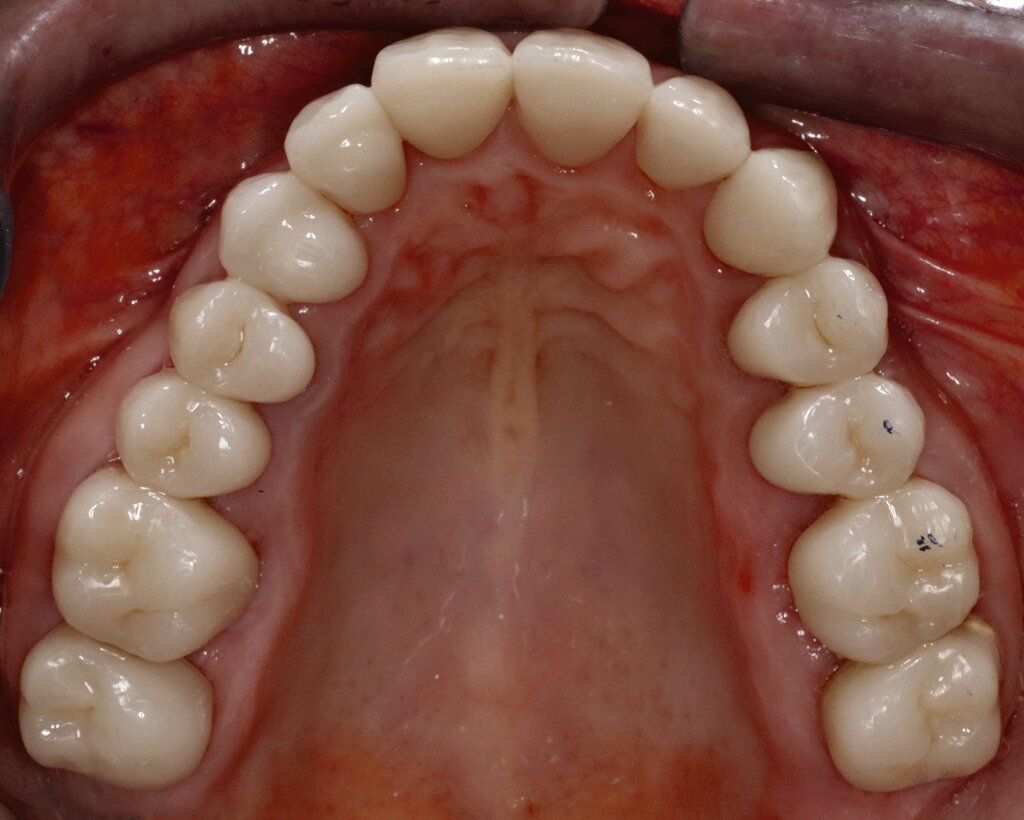

Eine 62-jährige Patientin stellte sich im Jahr 2025 in der CMD-Sprechstunde vor. Gemäß der allgemeinen Anamnese bestanden keine Vorerkrankungen. Die spezielle Anamnese zeigte den Zustand nach alio loco erfolgter prothetischer Rekonstruktion im Dezember 2024 mit festsitzendem Zahnersatz. Die Versorgung umfasste 14 Kronenrestaurationen (17–27) im Oberkiefer sowie zwölf Kronen (45–36) und zwei Implantatsuprakonstruktionen (046, 047) im Unterkiefer.

Mobilität des Unterkiefers eingeschränkt: Kieferöffnung aktiv ohne Schmerz 20 mm, aktiv mit myogenem Schmerz 32 mm, passiv 42 mm (Deflexion nach links, myogener Schmerz); unterdurchschnittliche Rechtslaterotrusion 4 mm und Linkslaterotrusion 6 mm (jeweils myogen schmerzhaft); Protrusion 4 mm (myogen schmerzhaft); Vertikaldimension unphysiologisch zu hoch (circa 2–3 mm) (Abbildungen 5 und 6).

Statische Vorkontakte 25/34 und 26/35 in geführter zentrischer Kondylenposition (entspricht dem subjektiven Erstkontakt) (Abbildungen 7 und 8) mit forcierbarem Gleiten in die maximale (Kronen)Interkuspidation circa 3 mm nach rechts (Abbildung 9).